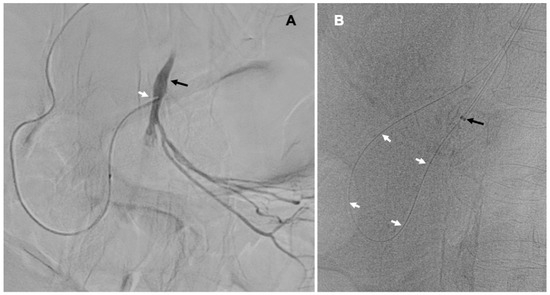

After predilation, there was a good inflow to the SMA and its branches (Figure 3). Finally, the 6.0/38 mm Omnilink Elite balloon-expandable stent (Abbott Vascular, Abbott Park, IL, USA) was implanted in the proximal part of the SMA. After stent implantation, there was a brisk inflow to the target artery and its branches.

Figure 3.

Catheter angiography after predilation of the proximal part of the superior mesenteric artery (black arrow), good inflow to this artery and its branches, thick arrow points the guidewire navigated through the branches of the celiac trunk; in the left upper corner of the picture after stent implantation.